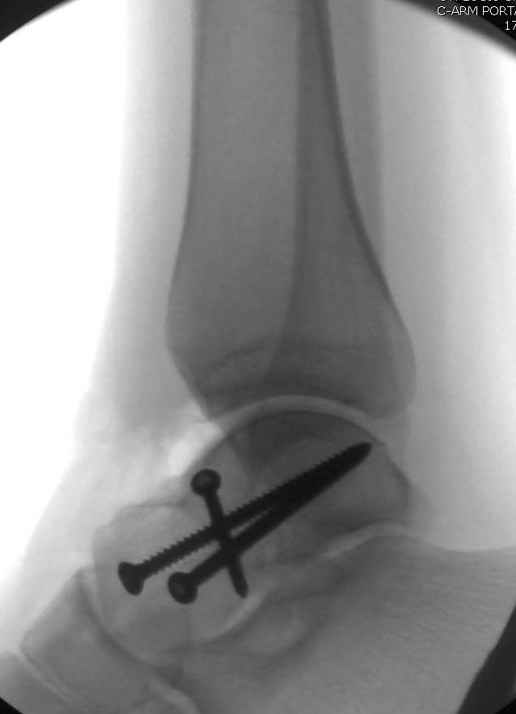

Вдогонку по поводу перелома таранной кости, больная 81, не страдает диабетом, перелом закрытый, в первый же день поступления ограничились временным наружным фиксатором (как на снимке).

Планировалась открытая фиксация после спадения отека, но больная пожелала лечиться по месту жительству в другом штате..

За пару недель насчитал 5 больных с переломом таранной кости, из них двое с двусторонним повреждением.

Из-за отека на стопе тактика лечения у всех была

одинаковая: временная наружная фиксация до спадения отека, при изолированных переломах они выписывались домой и через дней 7 госпитализировались на оперативное лечение.

Примеры на снимке...